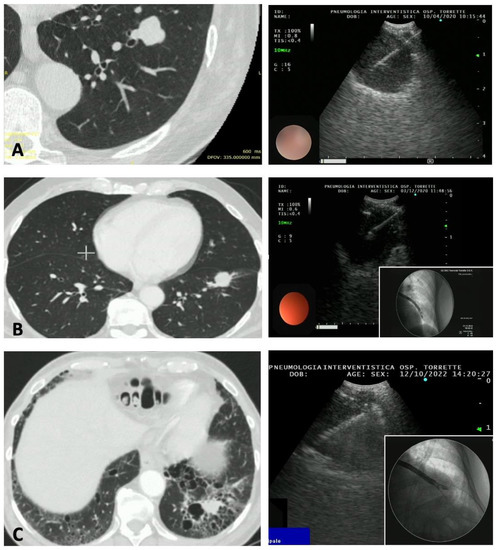

Figure 1 and Figure 2 show the CT findings and the paired ultrasonographic appearance of the pulmonary nodule in some of the patients included in the present series.

Figure 1.

Three cases of peripheral pulmonary nodules of the left lung approached with EBUS-TBNA for diagnostic purposes. (A) Carcinoid tumor of the lateral segment of the left lower lobe. (B) Adenocarcinoma of the lateral segment of the left lower lobe; in the inset, a fluoroscopic image was obtained during the procedure, showing the echobronchoscope close to the nodule. (C) Adenocarcinoma of the posterior segment of the left lower lobe. Emphysematous bullae are present around the nodule, making a percutaneous approach at high risk for pneumothorax.